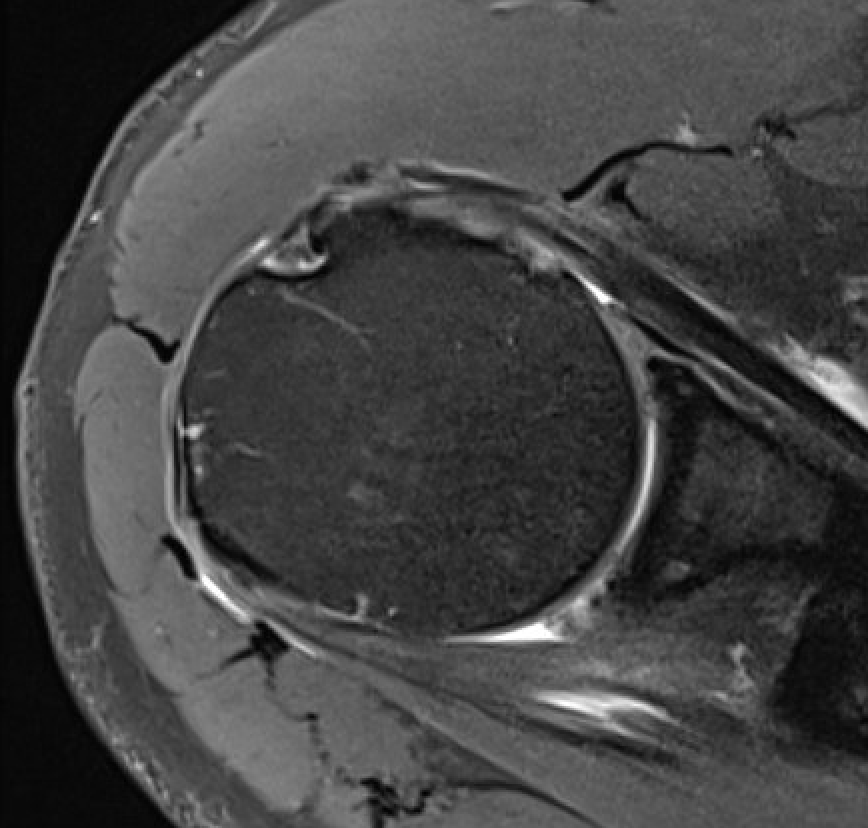

Comma Sign

Comma sign

- medially retracted subscapularis tear

- exposes the superior insertion of superior glenohumeral ligament / coracohumeral ligament

Full thickness retracted subscapularis tear with comma sign

Full thickness completely retracted subscapularis, loss of rotator interval and comma sign

Full thickness completely retracted subscapularis, loss of rotator interval and comma sign